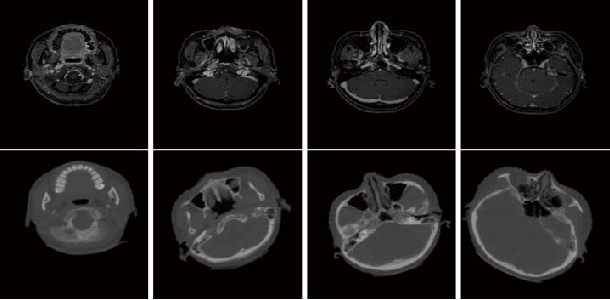

Abstract:The crucial components of a conventional image registration method are the choice of the right feature representations and similarity measures. These two components, although elaborately designed, are somewhat handcrafted using human knowledge. To this end, these two components are tackled in an end-to-end manner via reinforcement learning in this work. Specifically, an artificial agent, which is composed of a combined policy and value network, is trained to adjust the moving image toward the right direction. We train this network using an asynchronous reinforcement learning algorithm, where a customized reward function is also leveraged to encourage robust image registration. This trained network is further incorporated with a lookahead inference to improve the registration capability. The advantage of this algorithm is fully demonstrated by our superior performance on clinical MR and CT image pairs to other state-of-the-art medical image registration methods.

Abstract:Structure-preserved denoising of 3-D magnetic resonance images (MRI) is a critical step in the medical image analysis. Over the past years, many algorithms have been proposed with impressive performances. Inspired by the idea of deep learning, in this paper, we introduce a MRI denoising method based on the residual encoder-decoder Wasserstein generative adversarial network (RED-WGAN). Specifically, to explore the structure similarity among neighboring slices, 3-D configuration are utilized as the basic processing unit. Residual autoencoder, combined with deconvolution operations are introduced into the generator network. Furthermore, to alleviate the shortcoming of traditional mean-squared error (MSE) loss function for over-smoothing, the perceptual similarity, which is implemented by calculating the distances in the feature space extracted by a pre-trained VGG-19 network, is incorporated with MSE and adversarial losses to form the new loss function. Extensive experiments are studied to access the performance of the proposed method. The experimental results show that the proposed RED-WGAN achieves superior performance relative to several state-of-art methods in both simulated and clinical data. Especially, our method demonstrates powerful ability in both noise suppression and structure preservation.